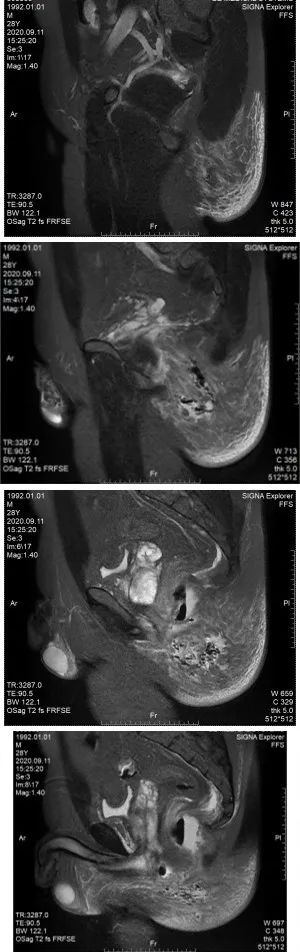

肛肠科主任医师再次查看病人,此时肛周MRI结果回示:直肠周围及左臀部、会阴部异常信号,考虑肛周脓肿并周围软组织水肿,建议增强扫描检查。图附下。

可见气液平面及组织间隙气体

白细胞及c反应蛋白均较前增高,且白细胞超过20×10^9/L,出现低蛋白血症,血红蛋白降低(贫血征兆),出现低钠、低钙电解质紊乱。感染较前次增加,提示重度感染,查看患者臀部红肿范围,1点位肿块红肿更加明显,范围较前增大,左侧臀部红肿范围亦有向后背部扩展迹象。结合肛周MRI,左侧臀部及会阴部皮下脂肪间隙模糊,见片状长T1长T2信号影,边缘不清,局部见斑片状气体密度影。主任医师查看病人后考虑:患者有坏死性筋膜炎可能,应立即行手术治疗,避免感染性休克及炎症的快速扩散导致生命危险。

2020-09-28复查MRI